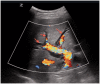

Right upper quadrant and epigastric abdominal pain are common presenting complaints in the emergency department. With increasing access to point-of-care ultrasound, emergency physicians now have an added tool to help identify biliary problems as a cause of a patient's right upper quadrant pain. Point-of-care ultrasound has a sensitivity of 89.8% (95% CI 86.4-92.5%) and specificity of 88.0% (83.7-91.4%) for cholelithiasis, very similar to radiology-performed ultrasonography. In addition to assessment for cholelithiasis and cholecystitis, point-of-care ultrasound can help emergency physicians to determine whether the biliary system is the source of infection in patients with suspected sepsis. Use of point-of-care ultrasound for the assessment of the biliary system has resulted in more rapid diagnosis, decreasing costs, and shorter emergency department length of stay.